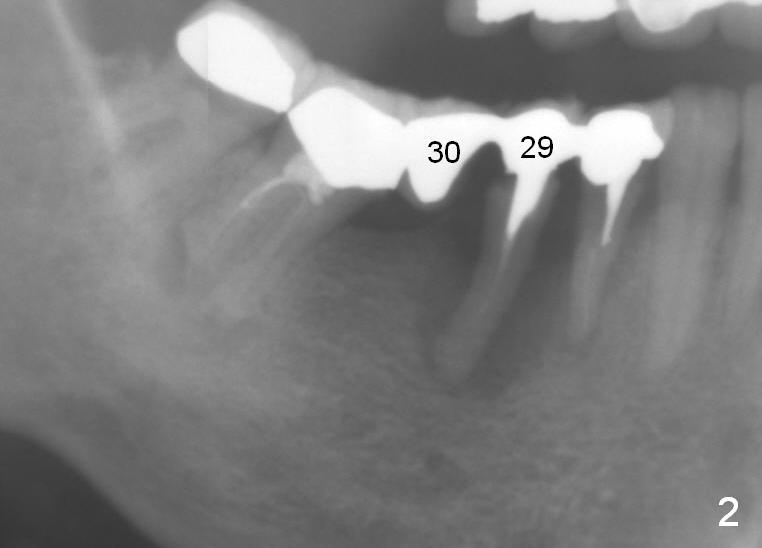

A 50-year-old lady (ZC) has poor dentition (Fig.1). The buccal gingiva of the tooth #29 is erythematous and edematous with deep pockets and severe bone resorption (Fig.2). Two units of the 5-unit bridge is going to be removed (Fig.3). A large implant is to be placed at the site of #29 (socket treated with Metronidazole), while a small one (probably 1-piece) at #30 (narrow mesiodistal space, Fig.4 green outlines). Be care of the mental loop (red dashed line). In fact, the patient wants to have #3 implant placed first.